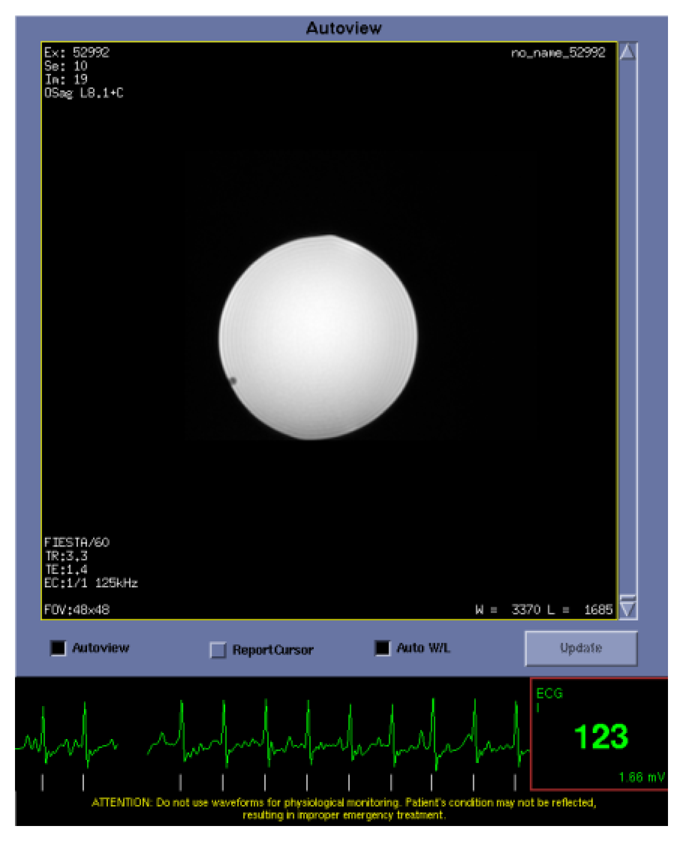

A waveform file provided by the device manufacturer produced a voltage using the sound card of a laptop computer to simulate the mECG and fECG signals. To test gating performance, the fECG signal measured through the MR compatible leads was converted into a digital gating pulse which was attenuated by 30 db and fed back into the standard MR ECG system. A balanced steady state gradient echo FIESTA sequence with SLT = 5 mm, in-plane resolution = 2 mm, NEX = 1, TR/TE = 3.3/1.4 ms was acquired with fECG gating at 123 bpm.

The fECG and mECG signals could be measured in real time using the Bluetooth interface (Figure 3). Occasionally, when the fetal and maternal ECG signals coincided, the fetal gating signal was lost due to software checks within the device which excluded it during this time. Test object images were acquired at the fetal heart rate (123 bpm) to demonstrate the rapid gating capability of the MR system (Figure 4).

In this study it has been demonstrated for the first time that it is possible to safely gate an MR scanner to the fECG using a modified fECG monitor and carbon fibre lead system. It was also possible to observe the mECG and fECG signals in real-time on a linked computer display using a Bluetooth interface available on the fECG device. The fECG signals reliably triggered a fast MR image acquisition sequence at the fetal heart rate from the simulated signal at 123 bpm. No interference between the gating system and the MR system was observed in terms of generated noise lines on the images in these preliminary studies.